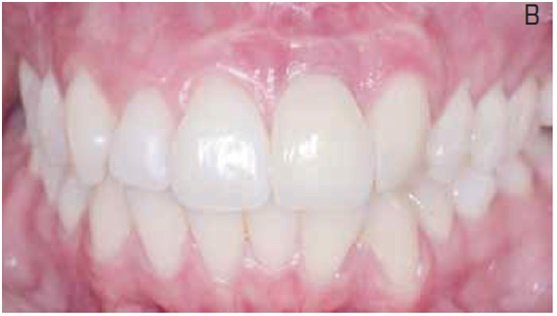

O tratamento consistiu na extração atraumática do dente e incisão de acesso na região periapical, para facilitar o procedimento de debridamento e minimizar o trauma mecânico na região cervical. Após remoção superficial do osso infectado e curetagem da região, um implante foi imediatamente instalado e a região apical foi preenchida com hidroxiapatita sintética para recuperar o volume perdido. No mesmo dia, uma provisória apoiada nos dentes adjacentes foi instalada e, após cinco meses, o paciente recebeu tratamento protético definitivo. Considerações sobre aspectos teóricos e práticos do procedimento são apresentadas e discutidas, com ênfase na previsibilidade estética do tratamento.